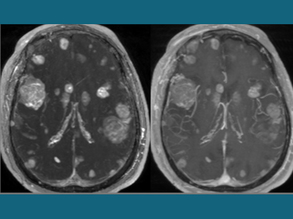

Brain Bug